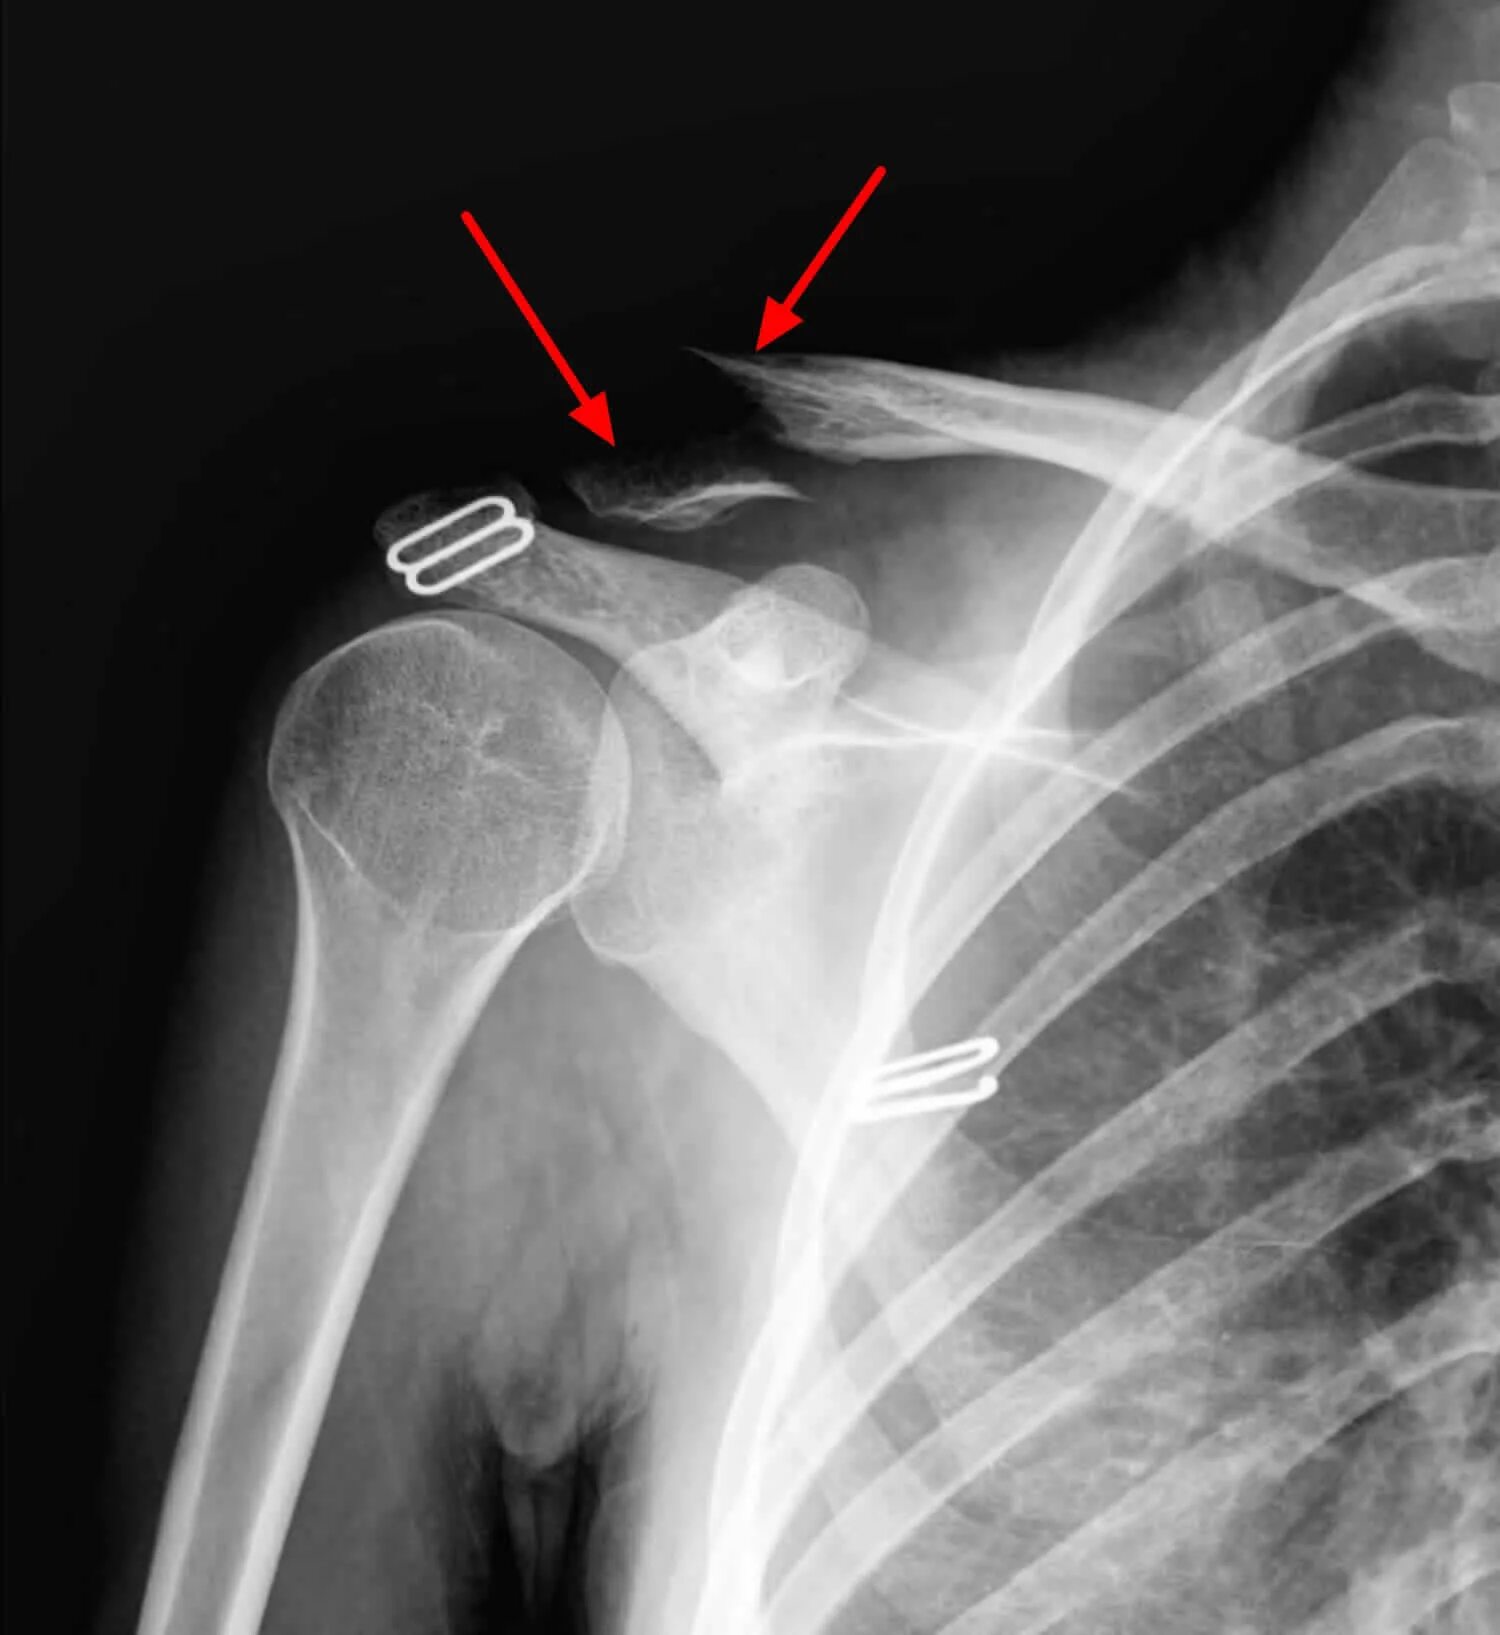

Перелом акромиального конца ключицы рентген. вывих акромиально-ключичного сустава рентген. разрыв акромиально-ключичного сочленения рентген. акромиальный перелом ключицы рентген.

Акромиально-ключичный сустав рентген. вывих акромиального конца ключицы рентген. подвывих плечевого сустава рентген. вывих акромиально-ключичного сустава рентген.

Рентген плечевого сустава трещина. перелом плечевого сустава рентген. рентген плечевого сустава перело. рентген плечевого сустава и ключицы.

Плечевой сустав рентген норма. перелом ключицы плечевого сустава рентген. перелом ключицы рентген. перелом плечевого сустава рентген.